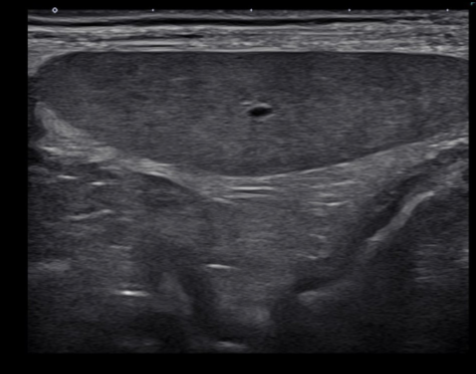

Anechoic

(black): no echoes

Example: fluid (like cysts or blood vessels)